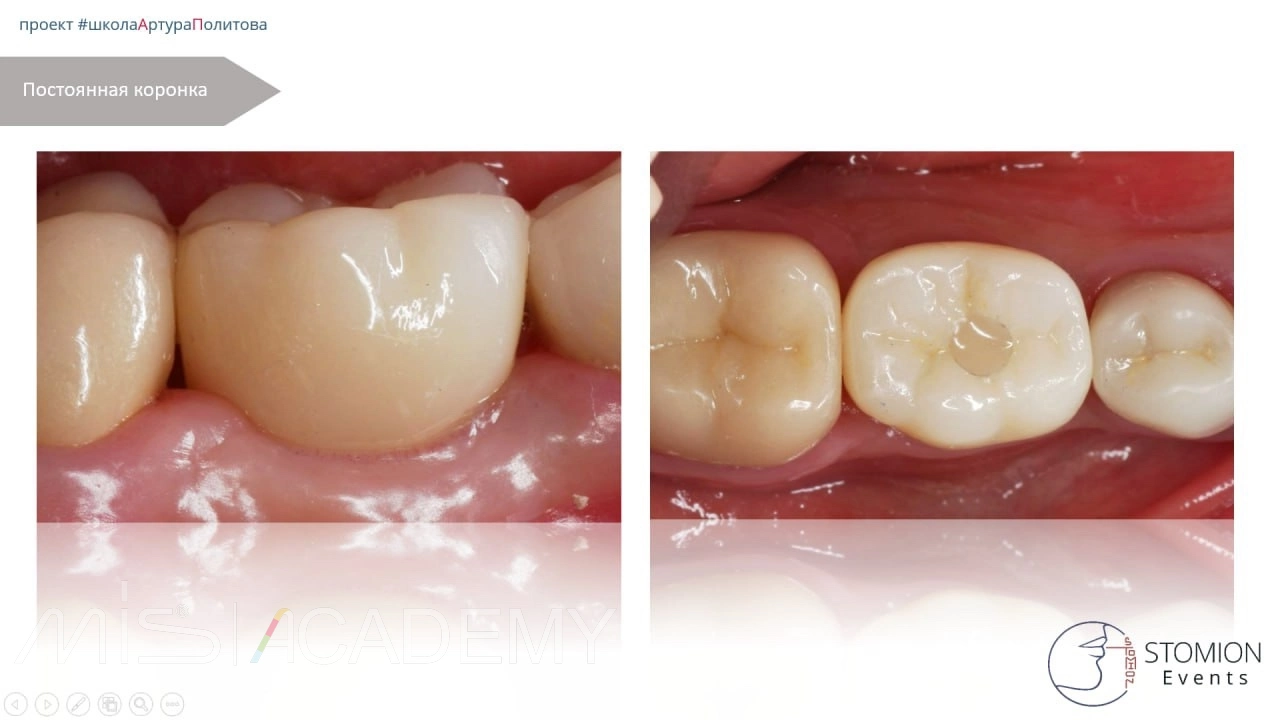

5. Через 3 месяца проведён контроль интеграции имплантата. Признаки стабильности и остеоинтеграции положительные. Выполнено постоянное протезирование.